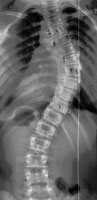

Возможность использования топографического мониторинга состояния больных сколиозом взамен рентгена была изучена на основе клинического материала школы-интерната №133 для детей больных сколиозом г.Новосибирска, где, начиная с 1995 года, проводились ежегодные обследования на ТОДП постоянного контингента больных параллельно с рентгеном. Среди больных по характеру течения заболевания выделены 3 группы: СФ - стабильная форма сколиоза, УПФ - умеренно прогрессирующая, БПФ - быстро прогрессирующая форма. Пример наблюдения больной с быстро прогрессирующей формой сколиоза приведен на рисунках ниже.

9,0 лет 10,4 лет 10,8 лет 11,4 лет 12 лет

PTI=1,0; Cobb=10° PTI=1,3; Cobb=17° PTI=1,9; Cobb=23° PTI=2,9; Cobb=38° PTI=3,6; Cobb=55°

За трехлетний период наблюдения в возрасте с 9 до 12 лет основная правосторонняя грудная дуга по углу Кобба спрогрессировала с 10 до 55°, т.е. средняя скорость прогрессирования составила 15° в год. Общий индекс нарушения формы дорсальной поверхности туловища PTI изменился с 1,0 (граница нормы и умеренно выраженных отклонений) до 3,6 (значительное отклонение). Следует обратить внимание, что в начале наблюдения туловище больной имело хороший баланс во фронтальной плоскости (вертикальная ось, проходящая через вершину межъягодичной складки, проходит также и через C7), а с возраста 10,8 лет стало явно нарастать нарушение баланса с отклонением туловища вправо, т.е. в сторону выпуклости основной дуги. Приведенный пример убедительно демонстрирует наглядность топографических данных и их большую информативность для решения задачи неинвазивного мониторинга состояния больных сколиозом.